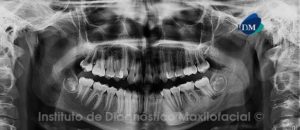

Paciente masculino, 11 años de edad es referido al Instituto de Diagnostico Maxilofacial (IDM) para evaluación general.A la evaluación de la radiografía panorámica (ortopantomografía) se